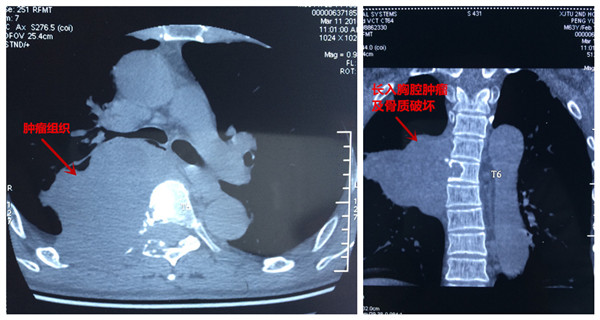

患者彭某,男,63岁,以胸背部疼痛5年,双下肢无力麻木半年之主诉入院,5年前无明显原因出现胸背部疼痛,影响夜休,就诊于当地医院,给与对症治疗,效果欠佳,背痛逐渐加重,长期服用非甾体类止痛药止痛,半年前无明显原因出现双下肢麻木、无力,走路不稳,进行性加重,未做治疗,2016年3月初就诊于当地医院,行胸椎MRI:胸6椎体水平椎管内外实质性暂未并胸6椎体附件、右侧第6肋骨骨质破坏,考虑恶性肿瘤可能,全身骨显像提示胸6椎体及右侧第6肋骨代谢异常活跃,恶性病变可能性大。当地医院拒绝治疗,为求进一步诊治,来我院门诊以“脊柱肿瘤”之诊断收入院。发病来食纳差,睡眠可,大小便正常,体重无明显变化。专科情况:脊柱生理弧度可,胸6棘突及附件压痛叩击痛阳性,半双下肢抽痛,双下肢肌张力可,肌力约3级,平乳头以下肢体感觉减退,无汗,双侧膝腱反射及跟腱反射阴性,双侧巴氏征阴性,左侧踝阵挛阳性。

患者入院后,王栋副主任,李锋涛主治医师高度重视,仔细询问患者病情,进行专科查体,分析以往患者的影像学资料,由于肿瘤组织生长巨大,严重压迫右肺,并且已经破坏了胸6椎体及其附件、右侧第6肋骨等,局部结构复杂,为了帮助手术方案的设计,我们采用3D打印技术,术前将肿瘤局部解剖结构打印成3D模型。邀请胸外科张维教授多次会诊,根据3D打印模型制定了详细的手术计划及围手术期治疗方案。经过严密的手术前准备,以王栋副主任、张维教授为主刀、李锋涛主治医师为助手,吴刚副主任医师、罗斌医师为麻醉医师,殷敏、马霞为配合护士,黄亚娟、王芳医师为术中诱发电位监护医师的手术团队努力下,手术顺利完成,成功切除了胸腔内、椎体旁及椎管内肿瘤组织,并进行了脊柱的重建。术后患者恢复良好,很快下肢感觉、肌力恢复,现患者正在康复中。